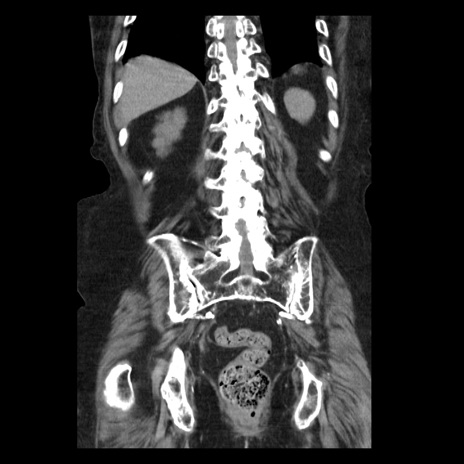

症例14(冠状断像)

【症例】 90歳代女性

【主訴】 腹痛・嘔吐

【現病歴】今朝から左側腹部痛を認めた。 経過観察していたが、嘔吐を認めたため来院。

【既往歴】 子宮癌術後

【身体所見】 意識清明、BP 127/54mmHg、P 98bpm Sp02 95%(RA)、BT 35.8°C、腹部平坦・軟腸ぜん動音聴取良好、右下腹部圧痛(+) 反跳痛なし

【データ】WBC 9800、CRP 0.46